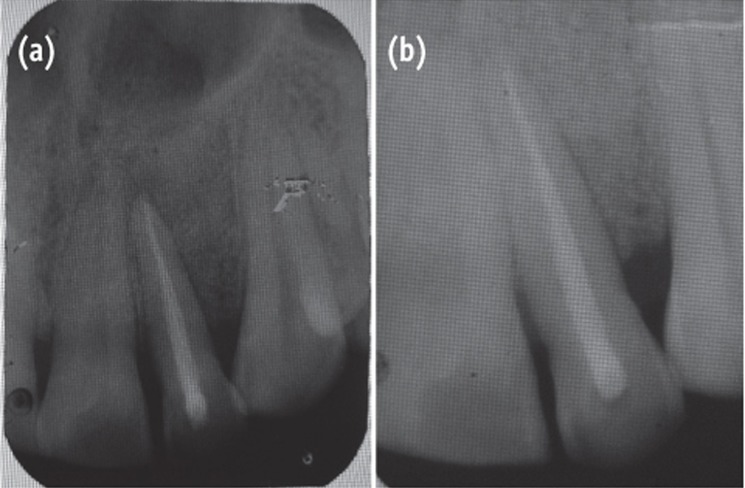

A 35 year old male patient reported to the Department of Periodontics with a complaint of pain in the upper left front tooth region associated with pus discharge for 2 months (

Figure 1). He also gave history of trauma around 7 years back and noticed discoloration of tooth with time but he took no treatment as the tooth was asymptomatic. On intraoral examination there were no carious teeth. Intraoral periapical X-ray (IOPA) was taken which revealed radiolucency along the distal side of the entire root surface to the apex (

Figure 2). Electric pulp testing was done to check the vitality of the tooth which confirmed that the tooth was non vital and the tooth was tender on percussion. Vertical probing depth was measured which was found to be 8 mm on distal side. Endodontic treatment was taken up first and then periodontal regenerative surgery was planned for treatment of defect.

Figure 1Preoperative view of discoloured maxillary lateral incisor.

Figure 2Preoperative radiograph showing radiolucency along distal aspect of maxillary lateral incisor to the apex.